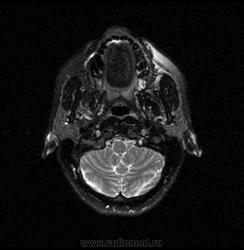

06.06.2011 МРТ - головы и шеи.

Пацентка 36 лет, с жалобами на припухлось в околоушной области справа.

В глубокой доле  правой околоушной железы  на фоне неизмененной паренхимы зона  гетерогенного по Т2, гипоинтенсивного по Т1  с единичными гиперинтенсивными включениями.При контрастировании- накопление контраста диффузное неоднородное и по периферии.Рискну предположить злокачественное образование ( аденокарцинома) с низкой степенью злокачественности( есть капсула, экспансивный рост).Сильно не расстреливайте.

Проблема в том, что перед челюстно-лицевым хирургом стоит распространенность любого объемного процесса, в данном случае все упирается в возмможную травму лицевого нерва и конечно же с дальнейшим его парезом, а ведь женщина  еще молодая. Образование имеет тонкостенную оболочку, по структуре неоднородно, с наличием кальцината, при этом МР-сигнал от окружающих анатомических структур(как костных так и мышечных) не изменен, т.е. об инфильтративном росте речи не идет, в какой то степени доброкачественное. В конкретном случае лицевой нерв с ретромандибулярной веной просто несколько оттеснен.

По гистологии аденома околоушной слюнной железы, но после удаления пока сохраняется парез лицевой мускулатуры, возможно временный.